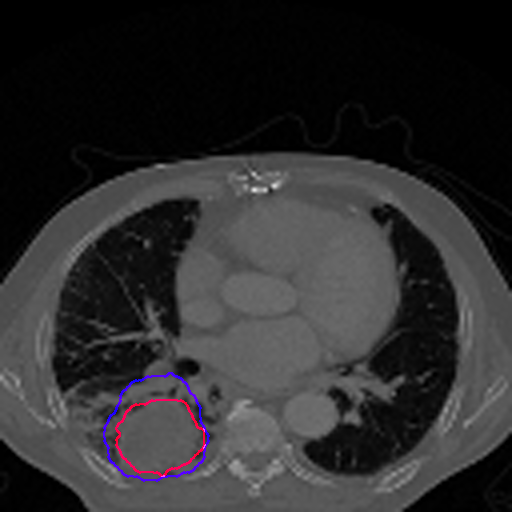

A qualitative analysis of our results reveals the strengths and weaknesses of our proposed model. In most cases, regardless of the size of the ground truth, our model predicts the tumor shapes very well. This is evident from Figure 4 where the ground truth and the prediction (by Deeply Supervised MultiResUNet) are shown in red and blue respectively. Although the tumors are in various arbitrary locations within the lung and appear in diverse sizes, the red and blue margins appear to coincide almost perfectly.

Figure 5 shows a comparison between predictions by the MultiResUNet model and Deeply supervised MultiResUNet model. It can be seen that the latter can delineate the tumor edges more accurately than the former. The ground truth (shown in red) and the prediction (shown in blue) have a more consistent alignment with each other in Deeply Supervised MultiResUNet’s prediction.